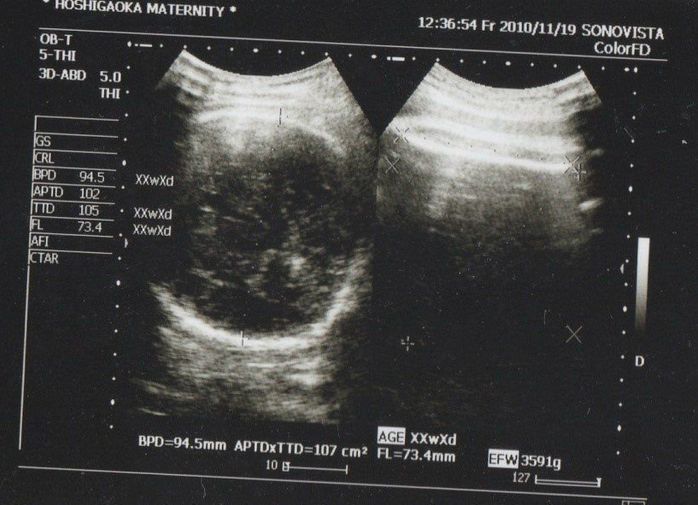

妊娠40週目のエコー写真

待ちに待った予定日にしたエコー検査です。頭部しか写っていませんが、なんとビックリ! 推定体重は3773g! おなかも大きめスイカがはいっているかのように特大サイズになっていて、歩くのもつらかった最終幕でした。